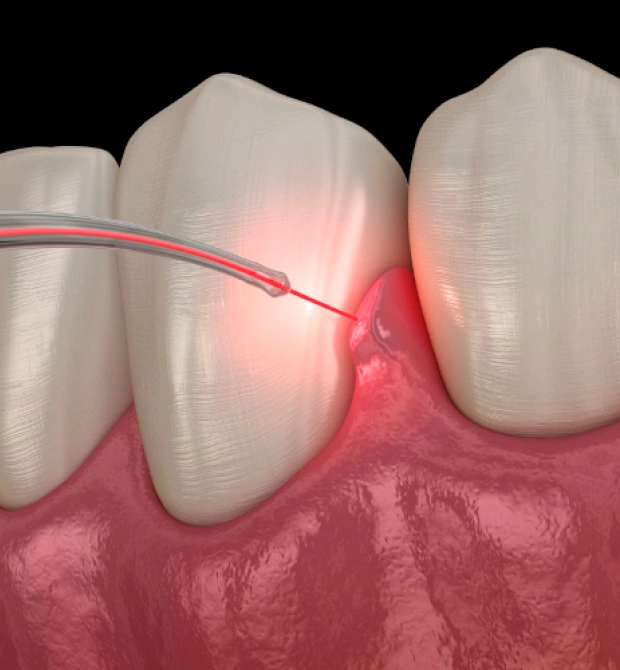

Laser Bacterial Reduction (LBR) is a cutting-edge dental procedure used to target and eliminate harmful bacteria below the gumline, improving gum health and preventing the progression of gum disease. At Dental Artistry in Irving, TX, we use state-of-the-art laser technology to perform LBR, offering a minimally invasive solution to treat and manage gum disease without the need for traditional surgical methods.

Laser Bacterial Reduction is a non-invasive procedure that uses a specialized laser to target harmful bacteria in the pockets of your gums, which is often the underlying cause of gum disease. The laser energy selectively kills bacteria while leaving the healthy tissue unharmed. This treatment is designed to reduce the infection in the gum tissue, reduce inflammation, and speed up the healing process.

LBR can be used alongside other periodontal treatments, such as scaling and root planing, to improve outcomes and help restore your gum health. The procedure is quick, comfortable, and requires no recovery time, allowing you to return to your daily activities right after treatment.